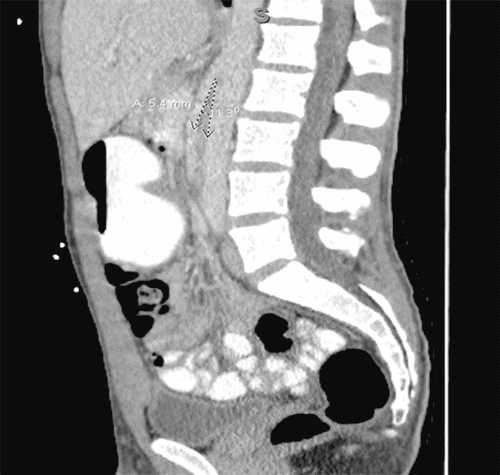

A 24-year-old man with a history of duodenal ulcer and delayed gastric emptying presented multiple times in the last three years to the emergency department (ED) for postprandial abdominal pain associated with nausea, vomiting and progressive intolerance to solids. During his most recent admission to the ED, his BMI was 18 kg/m2. A computed tomography (CT) scan of the abdomen and pelvis with contrast revealed narrowing of the aortomesenteric angle, measuring 11.3 degrees, and an aortomesenteric distance of 5.4 mm (Figure 1).

Figure 1. CT Scan of Abdomen and Pelvis with PO and IV Contrast. Published with Permission

Image depicting narrowing of aortomesenteric angle, measuring 11.3 degrees and aortomesenteric distance of 5.4 mm